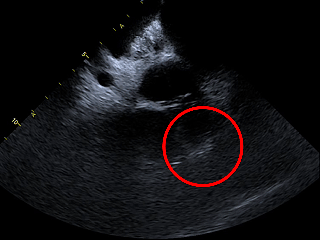

释放后评估,封堵器位置稳定且未见残余漏

封堵器在心耳内展开后造影,显示无残余分流,

且在超声下封堵器完全堵住心耳